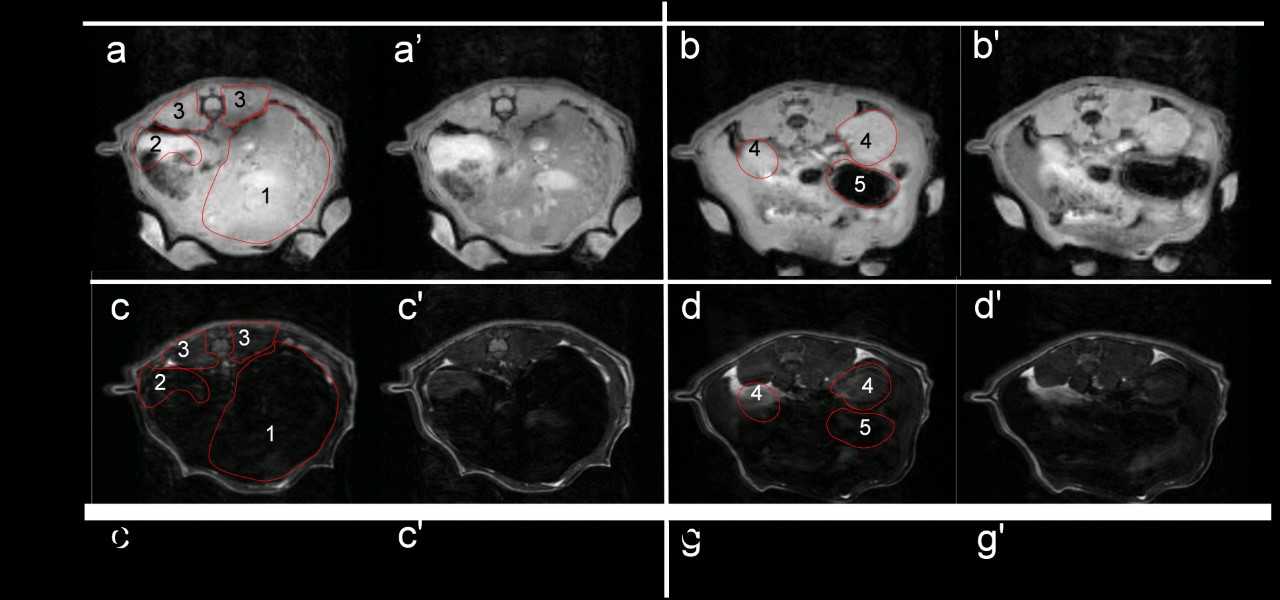

Tumores intramedulares

La mayor parte de los tumores primarios intramedulares son los gliomas, en particular los ependimomas (60%), y los astrocitomas de bajo grado (30 a 40%). Según el doctor Villarejo, un tumor intramedular se puede reconocer por una expansión focal determinada en parte por la localización anatómica, siendo el dolor el síntoma de presentación más frecuente.